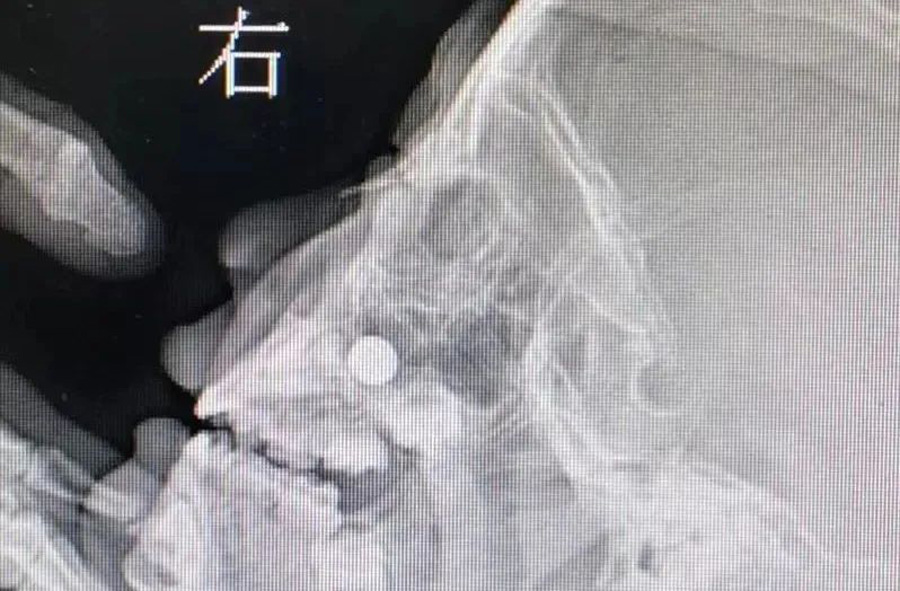

3月23日,120急救车将1名患儿送至啪啪网 。患儿3岁,来时明显看出鼻子不舒服。妈妈说,前一天儿子把纽扣电池塞右侧鼻子里了,但在当地医院没取出来。如果真的是纽扣电池,那就危险了,因为电池产生的腐蚀性物质及微电流会造成鼻腔黏膜腐蚀伤,甚至后期可能出现鼻中隔穿孔。门诊医生接诊后,未能看到鼻道中有明显异物,耳鼻喉科开放急危重症绿色通道。由于患儿及家长核酸结果未回报,耳鼻喉科医生在三级防护下做了鼻咽镜检查。在患儿下鼻道底部,发现有黏膜肿胀以及典型的纽扣电池异物放电导致的“冒泡”现象,但异物被肿胀的黏膜包裹,大小及形态显示不清。鼻咽部平片同样显示鼻腔底部有圆形金属异物。

由于异物位置特殊,以及患儿不配合,门诊不能顺利取出异物,急诊全麻取出是最好的办法。在全麻下,耳鼻喉科副主任李莉萍经过20多分钟定位、钩取,才将异物取出来。取出的纽扣电池颜色发黑,患儿右侧鼻腔黏膜也已被腐蚀成了黑褐色。经过给药处置、鼻腔消炎等治疗,第三天患儿出院回家了,后期需定期复查。